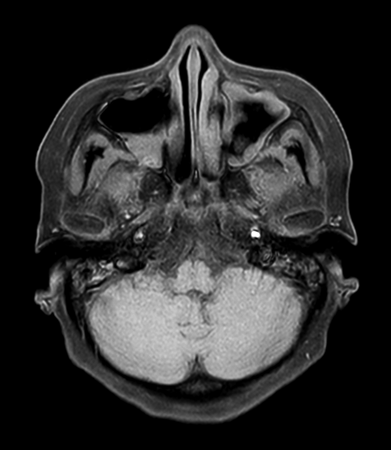

Axial mDIXON XD - T2w TSE (In Phase)